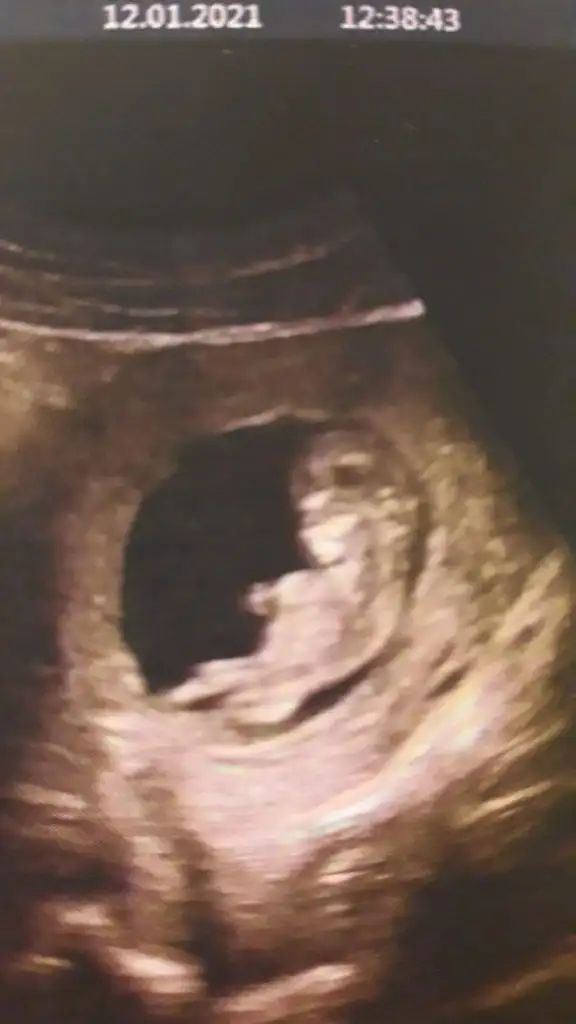

Ikra meyra Ikra meyra canım selam başka bir doktor bugün erkeğe benziyor dedi nub görüntüsü vermedi ama kalca ölçümü buydu sence nedir

Ben anlamadım bunu canım 11 12 13 haftalar paylaşın tekrar bakıp çizim ☺️ yada varsa başka USG paylaşın

Canım bu 12 artı 4 dü burda doktor kıza benziyor yüzde 80 demişti